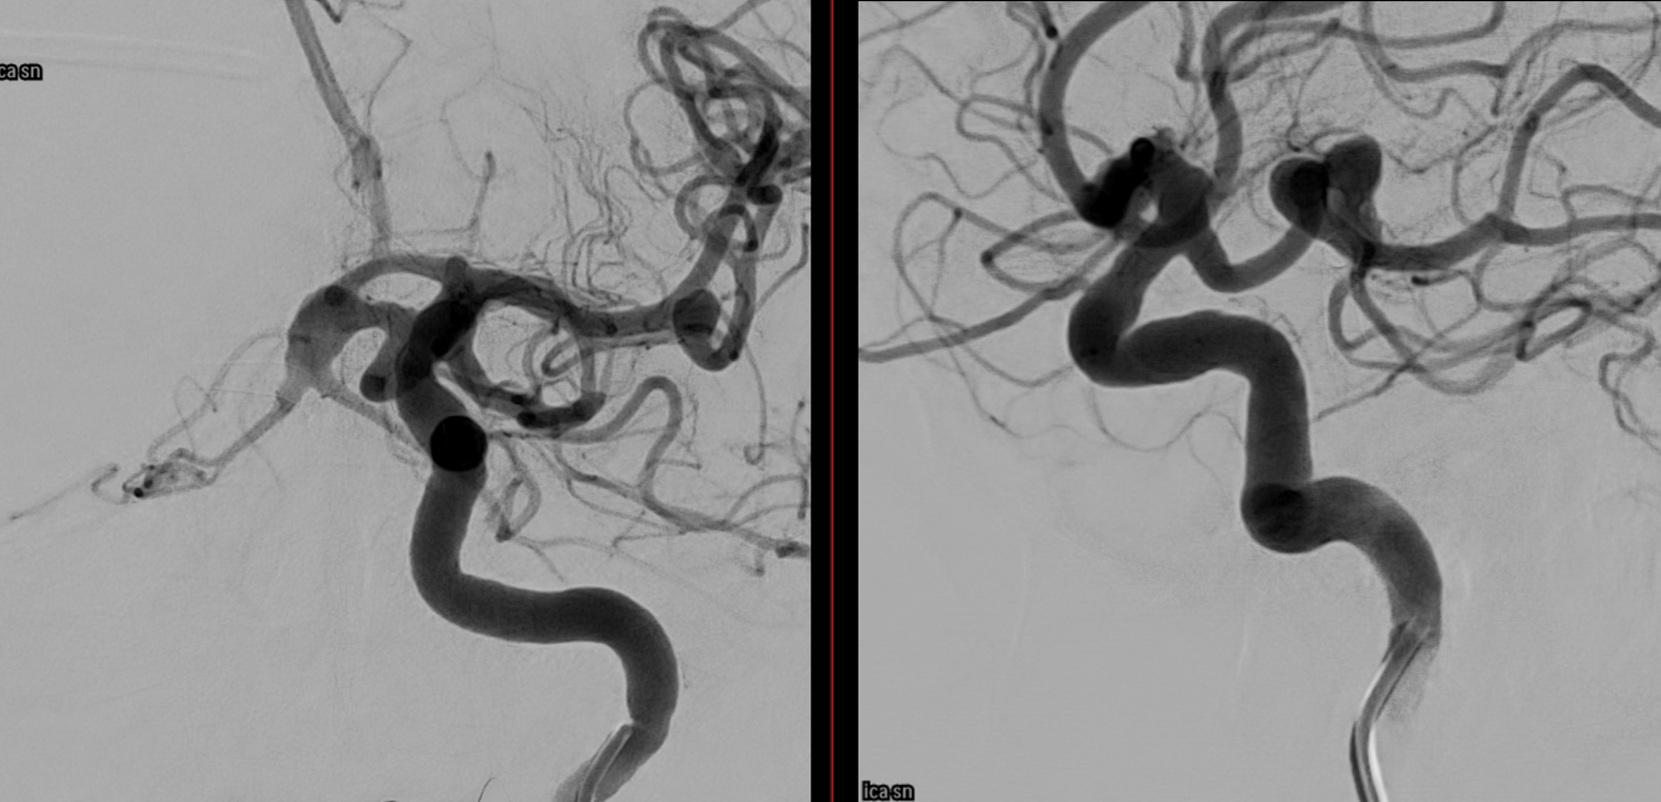

Post Rx. The key to this procedure, other than sophisticated understanding of the problem and the materials to be used, is a consistently effective antiplatelet state. Doing this without IIbIIIa in the lab for example risks major disaster.

At the 8 months follow-up, after passing from DAPT to SAPT, the aneurysm became smaller, with corresponding clinical improvement.

This is a key point — the success of treatment in aneurysms of this type is judged by cross-sectional imaging, not angio. With aneurysm shrinkage a good angiogram is guaranteed, while there are many examples of good-looking angiograms with moribund patients.